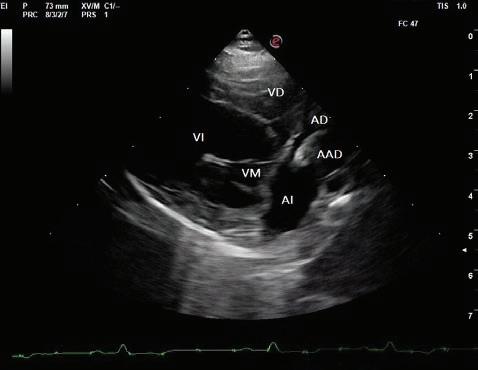

En el registro electrocardiográfico se observó un ritmo irregular en el que alternaron latidos sinusales y prematuros. La morfología del QRS de los latidos prematuros fue de complejos estrechos (<70 ms) y muy similares al latido sinusal precedente. La cadencia del ritmo era de dos complejos estrechos con intervalo RR estable. Este patrón de QRS estrecho-QRS estrechopausa se repitió de manera continuada y fue independiente de las fases del ciclo respiratorio. El primer QRS venía precedido de una onda P sinusal y el complejo prematuro de una P’ con diferente morfología, lo que se interpretó como actividad atrial ectópica. La realización de un ECG de 6 derivaciones permitió analizar la morfología de la onda P’, que fue positiva en derivaciones I, II, III y aVF, y negativa en derivaciones aVR y aVL (Fig. 3). El diagnóstico electrocardiográfico fue de complejos prematuros atriales frecuentes (ritmo bigémino atrial).

Figura 3. Electrocardiograma de 6 derivadas. Complejos prematuros atriales frecuentes (bigémino). Onda P’ positiva en derivaciones I, II, III y aVF, y negativa en derivaciones aVR y aVL.

La sintomatología y los hallazgos del examen físico observados en nuestra paciente fueron poco específicos. Las alteraciones en el ritmo y el pulso se consideraron consecuencia de la arritmia. En la mayoría de los casos publicados en medicina veterinaria, los animales no presentaban síntomas directamente atribuibles a la presencia del aneurisma6 y en nuestro caso no se consideró que la sintomatología tuviera relación con el aneurisma ni con la arritmia, ya que la intolerancia al ejercicio se resolvió sin que cambiaran los hallazgos del examen físico ni del electrocardiograma. Los signos clínicos más frecuentemente descritos en perros se asocian a arritmias supraventriculares con elevada frecuencia ventricular o a patologías concurrentes.1-6 En humanos un tercio de los casos de AAD son asintomáticos y los síntomas más descritos son palpitaciones, dolor de pecho y dificultad respiratoria, así como presencia de arritmias supraventriculares.8 La fibrilación atrial es la arritmia que con mayor frecuencia se ha asociado al aneurisma de aurícula derecha en veterinaria.2,4,5 En nuestro caso, como en los descritos en la bibliografía,1-6 la alteración del ritmo es de origen supraventricular y el análisis de la morfología de la onda P´ hace probable que el origen de los complejos prematuros sea el techo del atrio derecho.13 El diagnóstico electrocardiográfico fue de complejos prematuros atriales frecuentes (bigémino), que explica la alternancia en el pulso femoral y los cambios en la velocidad de los flujos de los tractos de salida en el Doppler pulsado. Este ritmo también podría ser compatible con un